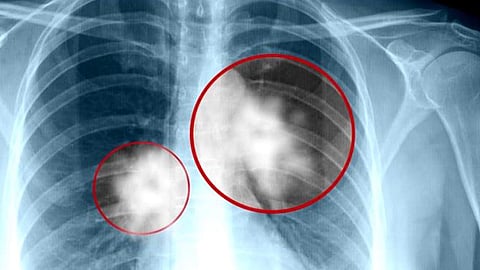

توصل علماء إلى علاج جديد لمرضى بعض أنواع سرطان الرئة القاتل، اعتبره العلماء «أكبر اختراق علاجي منذ عقود».

ووفق ما ذكر موقع «روسيا اليوم»، فإن علاج «Sotorasib» قرص يومي ثبت أنه يقلص الأورام لدى نصف المرضى المصابين بسرطان الرئة المتقدم غير الناتج عن التدخين.

ويصيب هذا النوع من السرطان واحدًا من كل ثمانية مصابين بسرطان الرئة، ناتج عن طفرة في الجين المعروف باسم «KRAS»، وهو شكل مميت من السرطان بشكل خاص؛ حيث لا تكون العلاجات الحالية فعالة إلا في حوالي 10% من المصابين به.